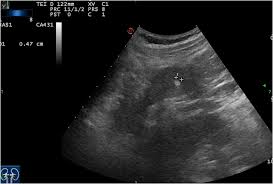

Die Ultraschalluntersuchung Sonografie ist meist die erste bildgebende Untersuchung bei Verdacht auf Blasenkrebs. Die Klassifikation Stadieneinteilung oder Staging genannt ist ein wichtiger Baustein für die Wahl der optimalen Therapie. Dabei kann der Arzt Blase Nieren und Harnwege begutachten.

Eine Ultraschalluntersuchung ermöglicht auch Blasensteine oder einen Blasentumor zu entdecken. Wirken Lymphknoten verdächtig veranlassen Ärzte in der Regel eine Biopsie oder Lymphknotenentnahme. Per Ultraschall lassen sich auch mögliche andere Ursachen für Beschwerden erkennen beispielsweise Nieren- Blasen-. Blasenkrebs kann als Folge einer Strahlentherapie entstehen. Blasenkrebs Mit der Diagnose Blasenkrebs hat der Patient nicht gerechnet. Sofern der Verdacht auf Blasenkrebs besteht nimmt der Arzt eine gründliche Untersuchung vor. Sie stellt zusammen mit der Biopsie Gewebeprobeentnahme die wichtigste Untersuchung für die Diagnose von Blasenkrebs dar. Ziel der Diagnostik ist eine möglichst frühzeitige Diagnosestellung und die Erhärtung oder Ausräumung des Verdachts auf Blasenkrebs. So stellen Ärzte beispielsweise bei Patienten mit einem Gebärmuttertumor ein erhöhtes Risiko für.

Die wichtigste Untersuchung zur Diagnose-Stellung ist die Spiegelung der Harnblase die sogenannte Zystoskopie. Es gibt keine Tumormarker im Blut die spezifisch für Blasenkrebs sind. Per Tastuntersuchung nimmt er dabei die Nierengegend den Unterbauch und die Geschlechtsorgane unter die Lupe. Blasenkrebs Mit der Diagnose Blasenkrebs hat der Patient nicht gerechnet. Liegt ein invasiver Harnblasentumor vor sind tiefgreifende Maßnahmen nötig. Wirken Lymphknoten verdächtig veranlassen Ärzte in der Regel eine Biopsie oder Lymphknotenentnahme. Die Ultraschalluntersuchung Sonografie ist meist die erste bildgebende Untersuchung bei Verdacht auf Blasenkrebs.